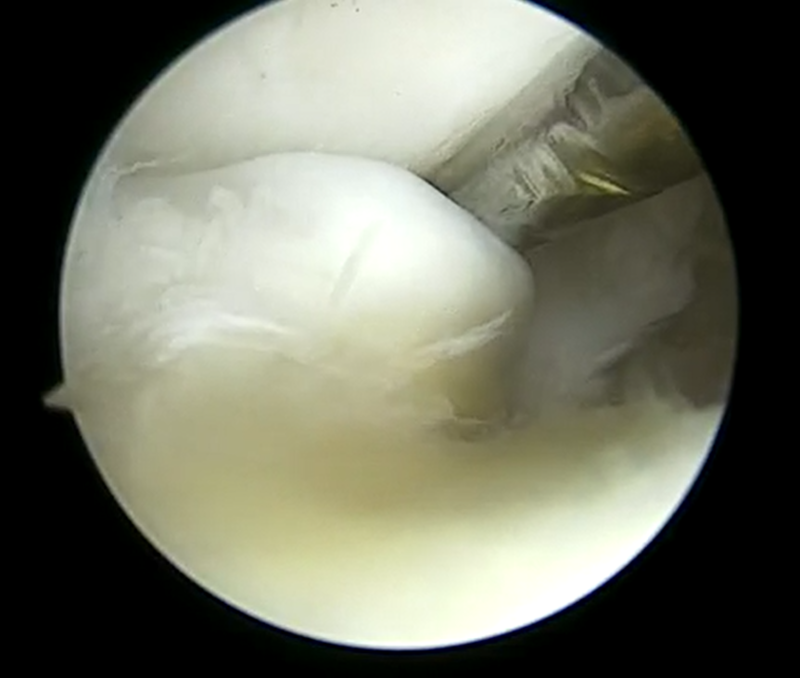

| 内側半月板問題なし | 外側半月板フラップ損傷 | 大腿骨側の軟骨損傷部 |

外側半月板と軟骨損傷の治療はなかなか難しいですね。術前に半月板断裂部が嵌頓してロッキングしている症状なのか軟骨損傷によるものなのか完全に把握するのは難しい時もあります。

今回は軟骨損傷により剥がれた軟骨片や半月板の断裂によるフラップ部分の引っ掛かりとそれにより膝の伸びが完全に出ないのが一番の問題と捉えて関節鏡視下手術を施行しました。術後膝が伸びないのが後方の筋腱拘縮の問題もありリハビリテーションも効果がとてもありました。